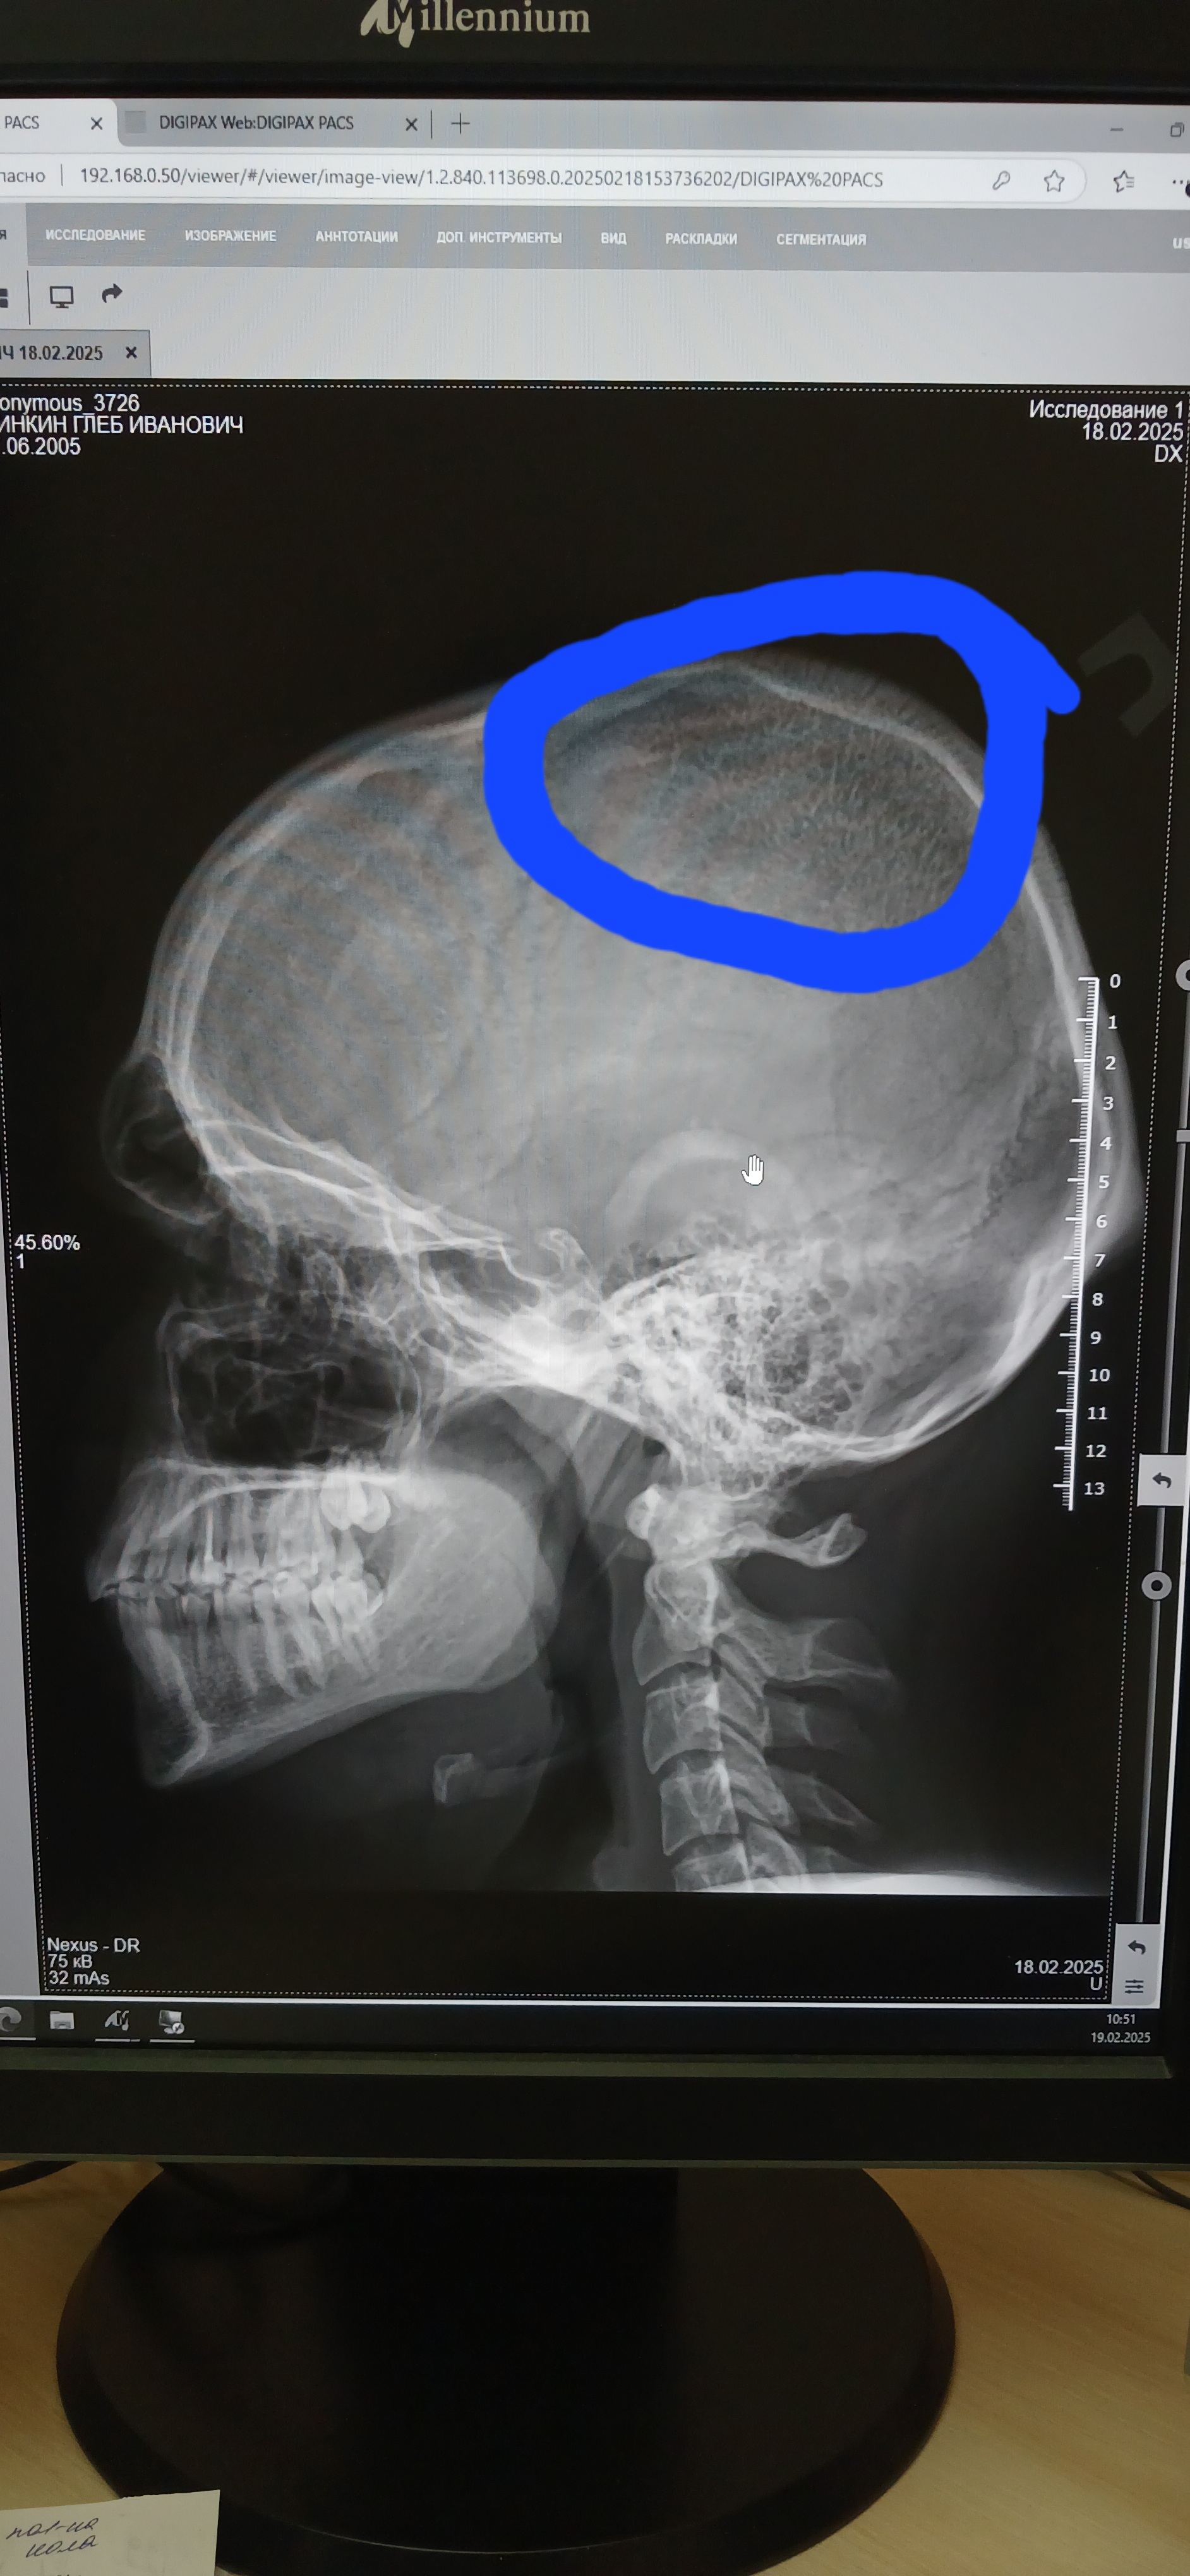

Здравствуйте,  подскажите пожалуйста,  что за структура костной ткани в теменной области?  Не видела раньше. Молодой человек,  19 лет. От невролога.  Беспокоят головные боли.

Структура кости в этом месте. Это норма?

Структура кости в этом месте. Может быть нормой?

Думаю, что это можно считать вариантом нормы.

Пожалуйста! В книге Королюка И.П. это  физологическое истончение теменной кости названо " пахионовы грануляции" , в " Клинической рентгеноанатомии" под редакцией Коваля как " венозная бухта", думаю, что второе точнее.Это видно и по прямой проекции.

- коллега, вы ставите нас в ложное положение: двигаете мышкой по монитору и меняете параметры изображения, это может оказаться гемангиомой свода черепа, а может ьыть нормой, вам на мониторе виднее